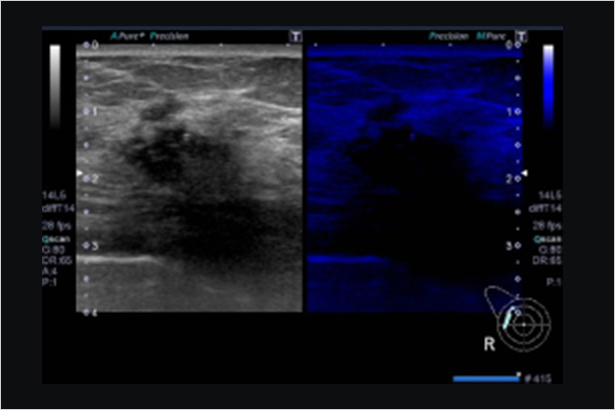

SMI帶來精細和清晰的彩色多普勒血流成像。SMI擴展了可見血流的范圍。低速微血流,SMI可以呈現

全方位的具有原始數據功能的彈性解決方案幫助您定位并評估淺表占位,準確性高,敏感度高,效率高,適用于不同臨床應用。在圖像中彩色編碼組織彈性的不同程度,使可疑組織可視化